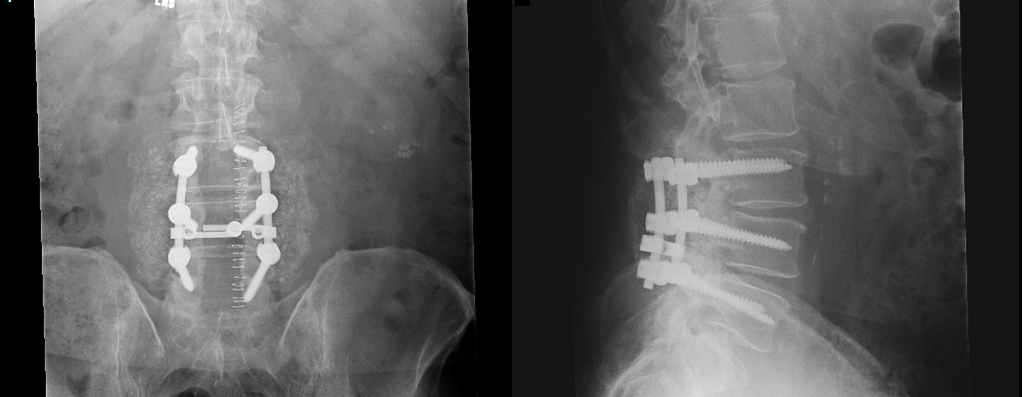

rmaynard 17,107 #4 Posted July 1, 2024 (edited) 5 hours ago, JimSraj said: I’ve also got L4 &L5 bulging discs and will be interested to hear how you recover. Mine are from a fall while pulling a snowblower backwards many years ago. The pain is nearly constant and getting worse lately. I’m considering options. If you don't mind another drop in here, I'll tell you about my L3 to L5 experience. I had what known as L3 through L5 laminectomy with instrumented fusion. That means that they removed the bony plate from the back of my spine, used rods and screws to stabilize, then wrapped the area with donated bone and cement. Before the surgery, I was in a lot of pain especially in the morning. Pain killers and walking helped. After the surgery, it took me about 12 months to fully resume my activities. However, my doctor was my age (old) and he restricted me from bending, lifting, and twisting. I don't regret the surgery. I would do it again in a heartbeat. However, I would use my wife's surgeon. She had the same surgery and her doctor (in his 30's) gave her no restrictions other than no more than a 20 pound lift. He said if it hurts, stop. She was back to normal in about 3 months. Eight plus years later I'm still moving and bending and twisting and lifting. I'm not pain-free, but what 74 year old man with osteoarthrosis is? Edited July 1, 2024 by rmaynard 1 Share this post Link to post Share on other sites

peter lena 9,851 #5 Posted July 1, 2024 @JimSraj @rmaynard obviousely every spine related issue is pain discomfort , mine was bone deuteriation in the pelvic outer areas , basically heavy bone rubbing , did the needed trimming , for assured clearance , used screws to enhance , secure , new fitting . jim ,went to a ORTHOPEDIC PARTNERS , location niantic conn , DR PETER WAGNER . very thorough , stages to actual work done . found anesthesia has a lot of effect on recovery the foggy state , was very confusing , paid attention to daily movement recommended stages , you are confused and unable to do what is required , so I started building on any positive stage . my recent walking gains with support , regular foam backed icing in a hard chair , take all the meds needed , definitely better . the doc said MACHO MEN have it the worst , because they cannot see themselves as weak , refuse help . that shopping cart , with slower vertical walking , has been very good for me .MAYNARD , can relate to pictures and learning how to move easier . also grab a afternoon nap every day , you cannot force this ,have to learn how your body is reacting , learn to stand comfortably , takes time , pete Share this post Link to post Share on other sites